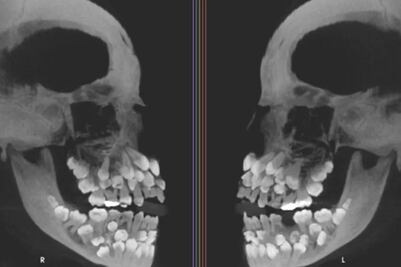

Este tratamiento se ha convertido en uno de los más solicitados sobre todo por sus fines estéticos, más que por sus ventajas a la salud de los dientes. ¿Qué riesgos o consecuencias pueden presentarse por querer tener una sonrisa perfecta?